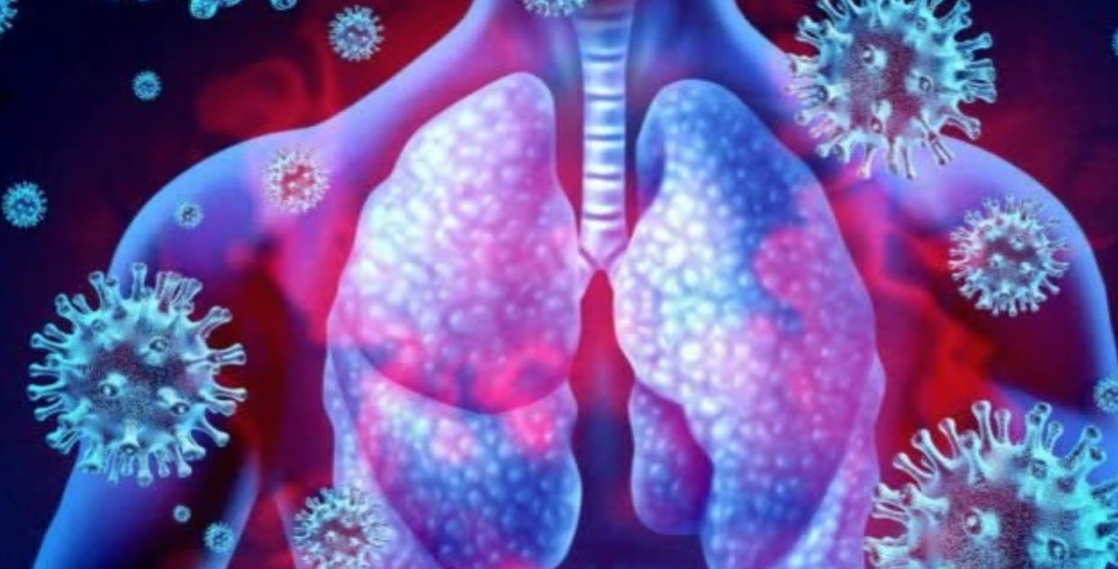

- 호흡기 감염 → 폐렴, 기관지염, 폐농양 (가장 흔한 원인)

패혈증은 초기에는 단순 감기나 몸살과 비슷하게 시작되기 때문에 놓치기 쉽습니다. 하지만 면역 반응이 과도하게 활성화되면서 전신 염증 반응이 빠르게 진행되는 것이 특징입니다.

- 호흡 증가(분당 20회 이상), 숨 가쁨 → 조직 산소 부족 상태

특히 호흡이 빨라지거나 정신 상태가 변하는 경우는 뇌와 폐에 산소 공급이 부족하다는 신호로 즉시 진료가 필요합니다. 고령자에서는 열이 없거나 오히려 체온이 떨어지는 경우도 많아 더욱 주의해야 합니다.

- 산소 치료 또는 인공호흡기 적용 → 조직 산소 공급